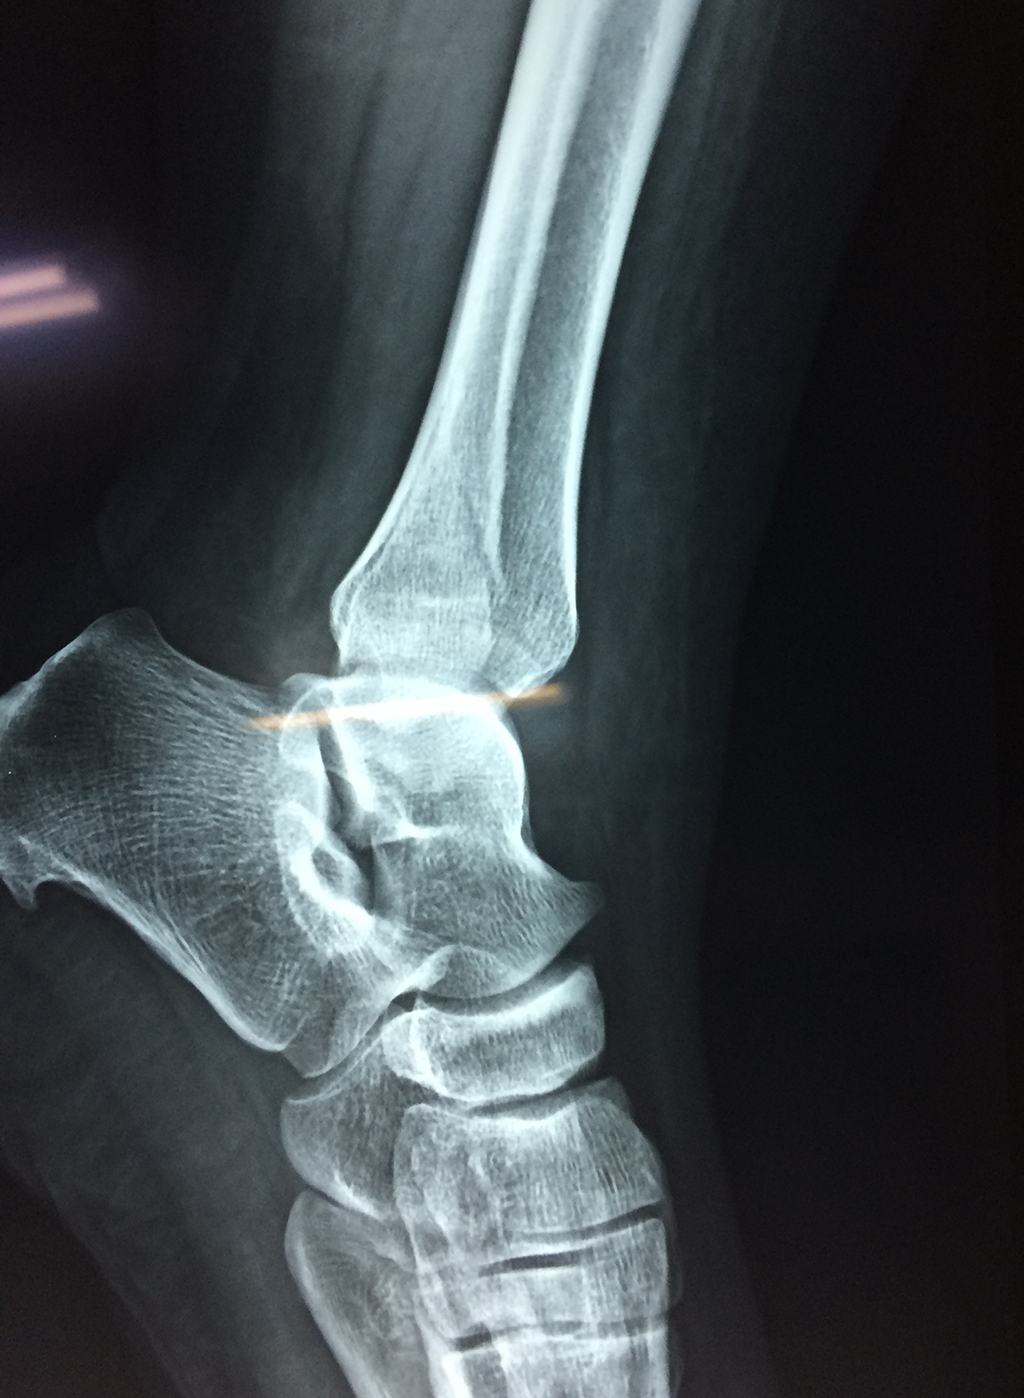

- Los extremos de los huesos están desalineados entre sí (desplazados).

- La fractura se extiende hasta la articulación del tobillo (fractura intra-articular).

Cuando se necesita cirugía, es probable que esta implique el uso de clavijas de metal, tornillos o placas para sostener los huesos en su lugar mientras la fractura se consolida. Los elementos de soporte pueden ser temporales o permanentes.